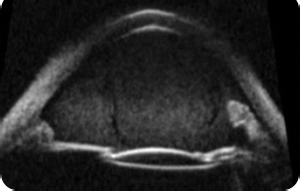

УЛЬТРАЗВУКОВАЯ ДИАГНОСТИКА Ультразвуковая Био Микроскопия

Диагностика переднего отрезка с высоким разрешением

Существует много случаев, когда детальное ультразвуковое обследование переднего сегмента с высоким разрешением может быть полезным для оценки состояния зрительного органа. Ультразвуковой биомикроскоп VuMAX® лучше других, известных сегодня методов, обеспечит офтальмолога изображениями интересующих участков.

Зачастую из-за непрозрачности сред очень трудно идентифицировать опухоли, повреждения, увеиты и подобные им патологии. Высокая разрешающая способность VuMAX® обеспечивает четкую визуализацию структур, играя при этом, важную роль в диагностике и лечении подобных патологий.